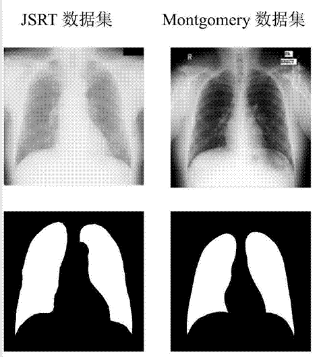

正是由于 AI 具备对大量数据学习与判断的能力,通过对大量 X 光片数据集的训练,智能体能够在很短的世界内达到接近人类的识别准确度。

早在 17 年时,吴恩达等研究者借助国立卫生研究院公布的 10 万幅 X 光片对人工智能算法进行训练,就能使该智能体在短短两个月的时间,检测精度超越放射科医师水平。

• 其次是图像识别,主要应用于数据分析环节。通过对影像等多媒体医疗非结构化数据的识别与分析,从而实现对具有临床意义信息的提取。

AI 病理诊断技术可大幅缩短医生的工作量,提高放射学、病理学等依赖医学图像支持的专业的诊断效率和准确性。因此,AI 研习社这次以 AI 医疗为主题,开设了「肺炎 X 光病灶识别」挑战赛。

大赛主页提供了「肺炎 X 光片」相关的数据集,包括了训练集 20013 张以及测试集 6671 张。比赛任务也非常明确:只需编写相应代码,训练模型完成对测试集图片内容的正确识别即可~